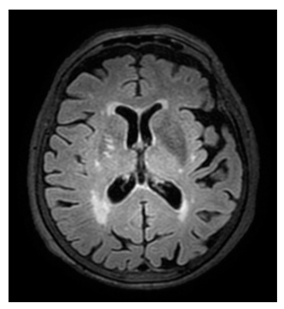

- White matter hyperintensities (WMH): Classified using the Fazekas scale (0–3) [21].

Regarding measurements of cerebrovascular disease, there were numerous statistically significant differences between MD and controls, namely the following: higher mean Fazekas score in MD (1.1 ± 0.8 in MD vs. 0.75 ± 0.8 in controls, p = 0.013); higher EPVStotal in MD (1.20 ± 0.9 in MD vs. 0.71 ± 0.8 in controls, p = 0.001);